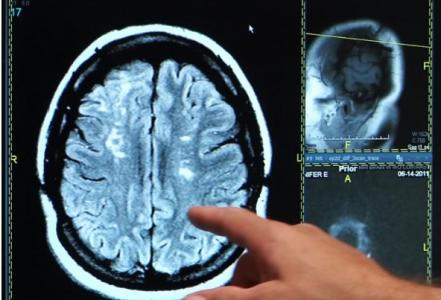

Cette découverte d’une équipe de l’Université de Göteborg pourrait permettre une récupération plus rapide et plus efficace après un accident vasculaire cérébral (AVC). Il s’agit d’une « simple » molécule, « C3a peptide », produite naturellement dans le corps. C3a a la capacité de créer de nouvelles synapses dans le cerveau. Ces données obtenues à ce stade chez l’animal et présentées dans la revue Brain confirment l’efficacité du composé.

Les chercheurs suédois administrent C3a ou un placebo à 28 souris, modèles d'AVC, une semaine après l'événement, et via des gouttes nasales. Les souris traitées récupèrent beaucoup mieux et plus rapidement : concrètement, elles sont capables d'utiliser à nouveau la patte paralysée par l'AVC. L'analyse montre également que C3a permet, en fait, la génération de nouvelles cellules nerveuses et la création de nouvelles synapses entre les cellules. Un processus que beaucoup considèrent comme clé pour la récupération de la fonction cérébrale.